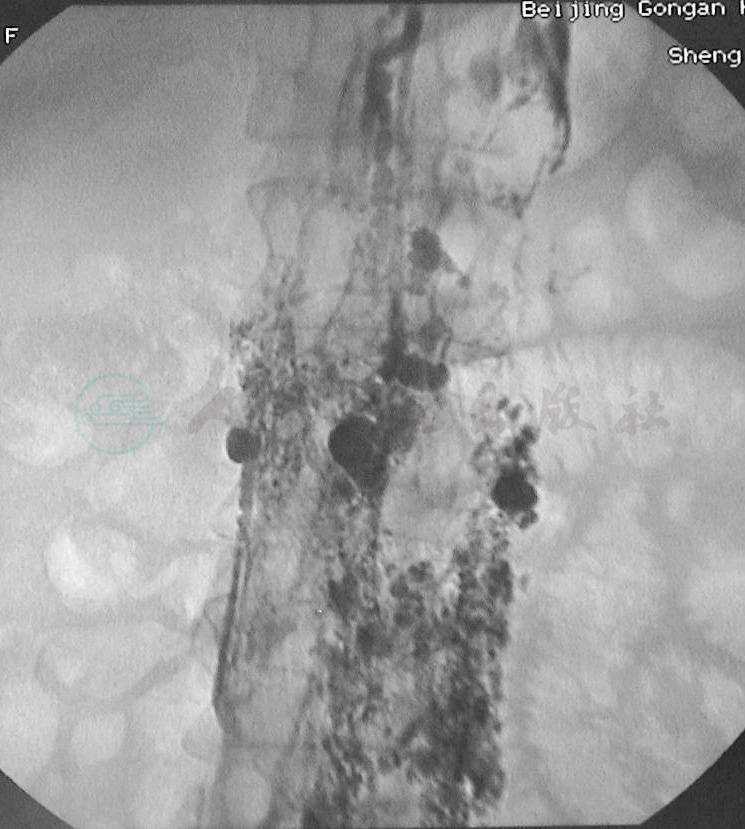

图9直接淋巴管造影显示盆腹膜后淋巴管扩张、迂曲、反流、串珠样改变

图10直接淋巴管造影显示脊柱前淋巴管扩张、淋巴管囊性变

图11直接淋巴管造影:腹段侧位片,显示脊柱前淋巴管扩张,串珠样